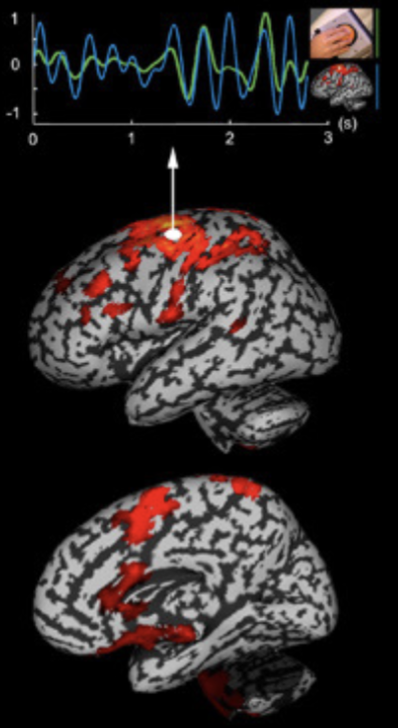

Event-related potentials

Analysis allows researchers to map the brain’s EEG response to environmental stimuli

In this examples, a characteristic waveform emerges

when responses to the presentation of a tone are average over 100 trials

Magnetoencephalography (MEG)

Electrical activity in the brain generates measurable magnetic fields

Electromagnetic fields generated by the brain

Cannot take activity from all over the brain

Difference from EEG; conductivity of the tissues inside the skull has little effect on the magnetic fields outside of the skull